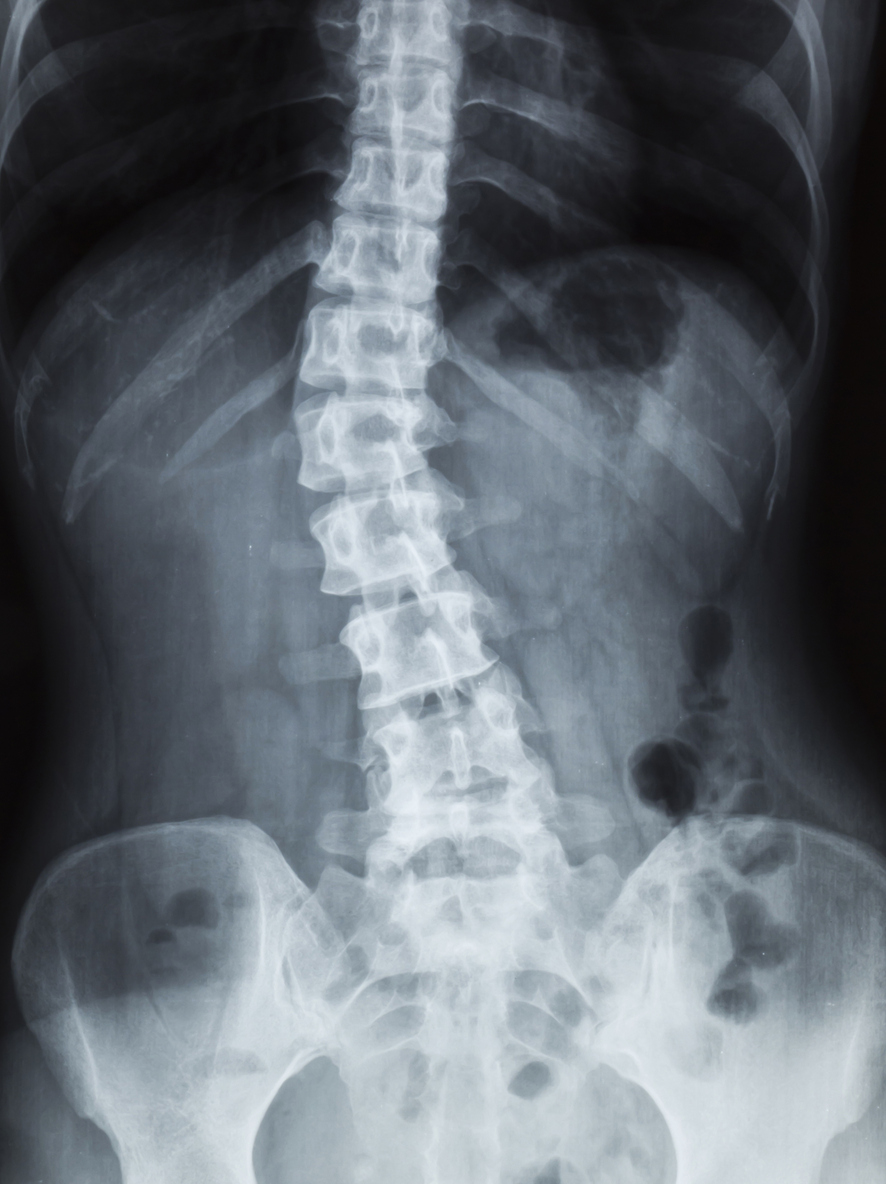

Scoliose Bascule Du Bassin . 8 choses que Vous devez Savoir sur la Scoliose YouTube En cas de scoliose, la colonne vertébrale présente une torsion. Même si la bascule du bassin pourra être traitée localement, le chiropracteur cherchera à identifier la « cause profonde » de ce problème, telle que notamment:

Source: sscopenfc.pages.dev Déformations Rachidiennes (scoliose, cyphose) Institut de Chirurgie du Dos Paris , L'examen physique, l'étude des antécédents médicaux et les tests d'imagerie tels que les radiographies ou les IRM peuvent être utilisés pour évaluer la gravité et l'étendue de ces affections Elle s'accompagne souvent d'une scoliose de compensation.

Source: wholderjvc.pages.dev Comprendre, prévenir et soulager la scoliose via l'Ostéopathie , La bascule du bassin peut entraîner des douleurs musculaires, une boiterie, et est souvent traitée par rééducation et semelles orthopédiques. L'examen physique, l'étude des antécédents médicaux et les tests d'imagerie tels que les radiographies ou les IRM peuvent être utilisés pour évaluer la gravité et l'étendue de ces affections

Dépistage et symptômes de la scoliose Dossier . La bascule de bassin est une asymétrie de hauteur entre les 2 côtés du bassin. Asymétrie costale ou signe de la lucarne (un espace prononcé entre le bras et le dos)